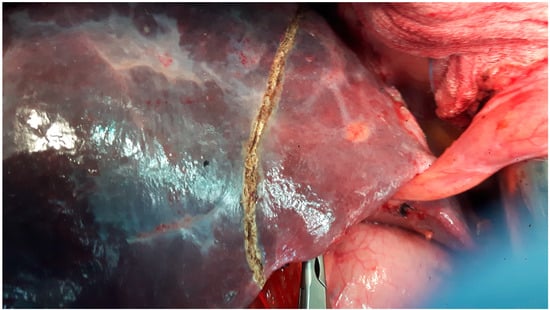

2. Materials and Methods

2.1. Design and Setting